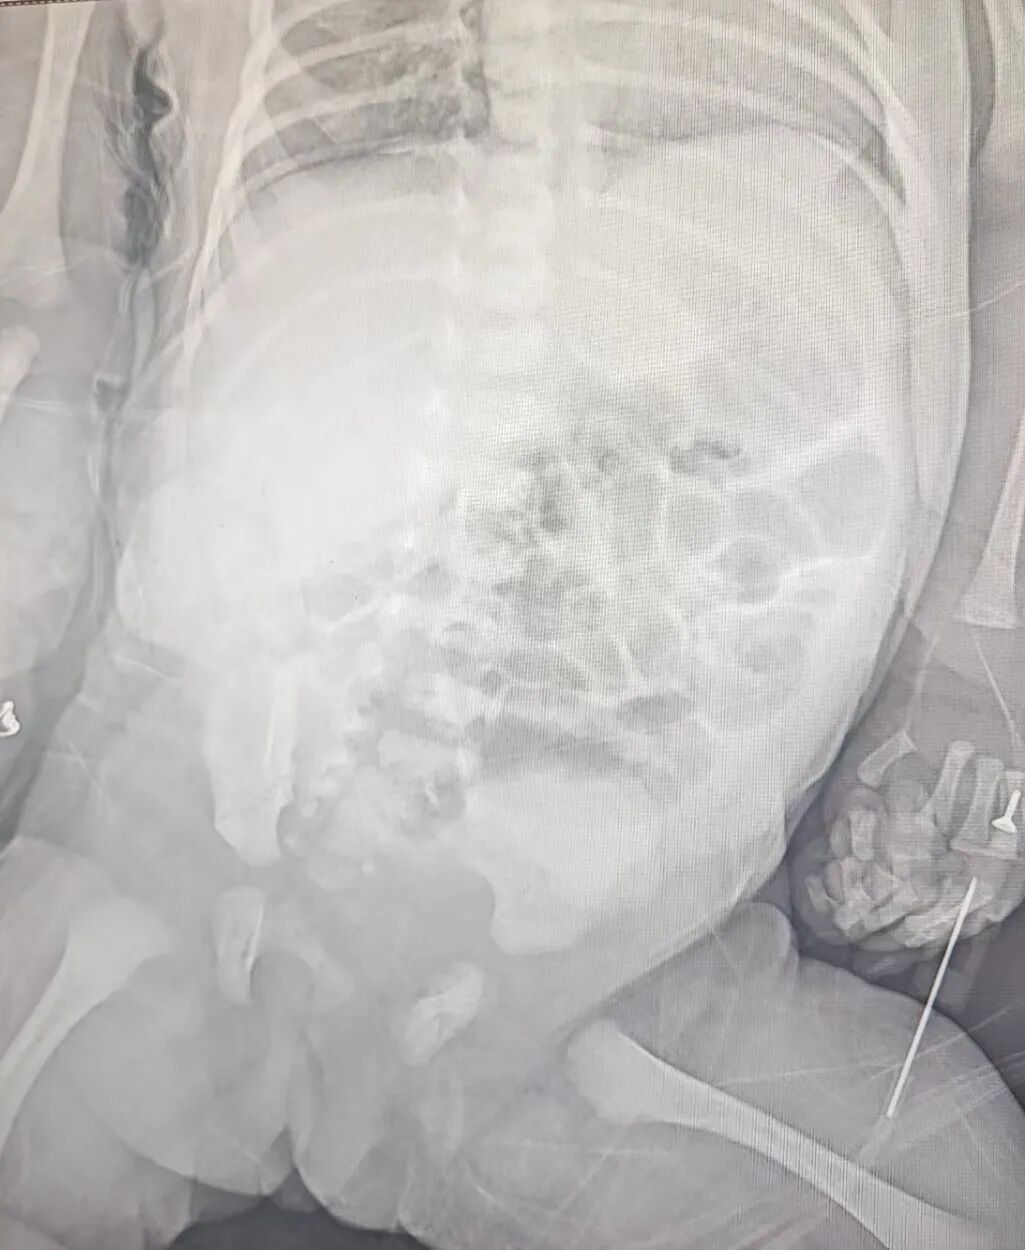

罕见!新生儿自发性脾破裂出血,青岛市妇女儿童医院新生儿外科团队争分夺秒止血保脾

近日,青岛市妇女儿童儿童医院新生儿外科团队凭借精准的病情诊断、快速的应急反应和成熟的手术操作,成功救治一名出生仅5小时就发现异常,继而确诊罕见自发性脾破裂的危重新生儿。